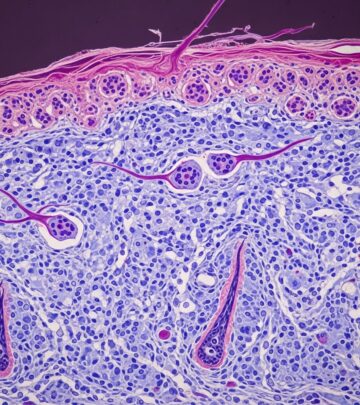

Fibrofolliculomas in Birt-Hogg-Dubé Syndrome Images